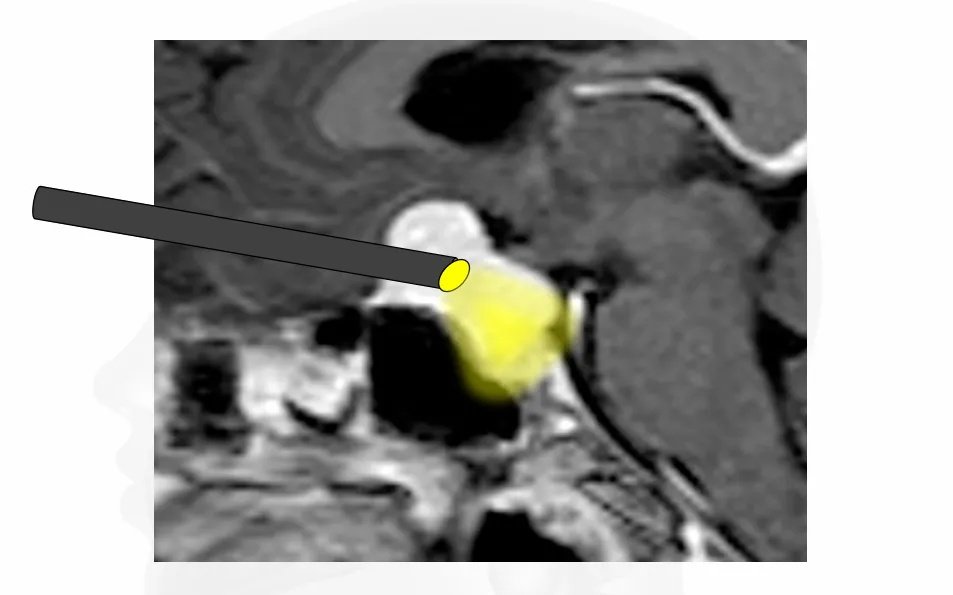

▼福教授经眉弓锁孔入路示意图交流

案例一:“经眉弓锁孔入路”全切蝶眶脑膜瘤

▼用磨钻“打孔”

▼取出肿瘤瞬间